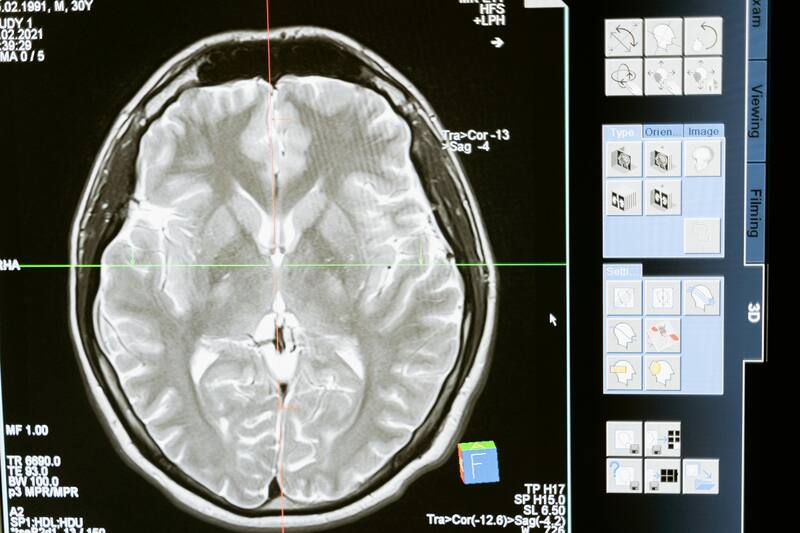

Para medir el impacto de la vida en gravedad cero, los expertos analizaron el comportamiento y conectividad cerebral de un grupo de astronautas que pasaron al menos 6 meses en el Espacio a través de resonancias magnéticas hechas durante la realización de tareas de memoria de trabajo espacial (MTE, o spatial working memory SWM en inglés) que representan la habilidad de mantener la información espacial activa en la memoria de trabajo durante un breve periodo de tiempo.

Así, el estudio pudo comprobar que si bien la actividad y el rendimiento cerebral no se ven mayormente afectados por la gravedad cero, sí se evidenciaron reducciones significativas en la conectividad cerebral principalmente en la circunvolución occipital superior (cuyo rol es interpretar la orientación, la forma, los colores y el movimiento), y entre la circunvolución occipital media izquierda (que trabaja con el movimiento visual) y la circunvolución parahipocampal izquierda (que ayuda con el orden temporal de la memoria episódica); el cerebelo izquierdo (encargado de tareas visoespaciales y de la memoria verbal) y el córtex occipital lateral izquierdo (que interpreta y procesa las imágenes que ingresan a través de la visión) antes y después de los vuelos al Espacio.